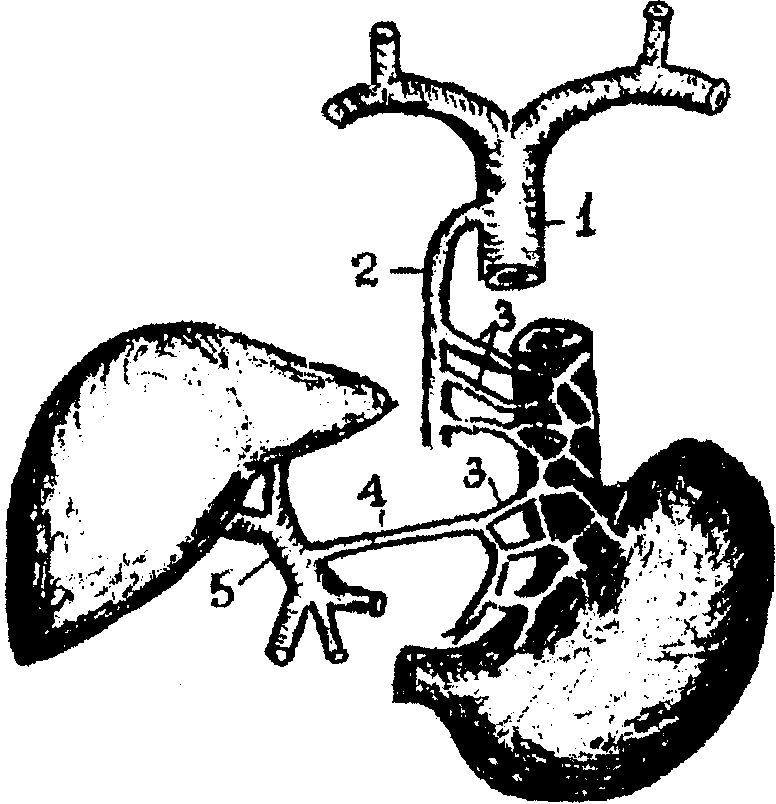

Анастомоз в стенке кардиального отдела желудка и брюшной части

пищевода (рис. 1.22а).

От венозного сплетения грудной части пищевода vv. esophageales впадают в v. azygos и в v. hemiazygos (система верхней полой вены), от брюшной части - в v. gastrica sinistra, которая является притоком воротной вены.

При портальной гипертензии венозное сплетение в нижнем отделе пищевода чрезвычайно расширяется, приобретает характер узлов, легко травмирующихся при прохождении пищи и дыхательных экскурсиях диафрагмы. Расширение вен пищевода резко нарушает функцию кардиального сфинктера, вследствие чего наступает зияние кардии и забрасывание кислого желудочного содержимого в пищевод. Последнее вызывает изъязвление узлов, что может привести к кровотечению.

| Рис. 1.22а. Схема анастомоза в области кардиалыюго отдела желудка и брюшной части пищевода. 1 - v. cava superior:, 2 - v. azygos; 3 - vv. esophageales; 4 - v. gastrica sinistra. 5 - v. portae. |